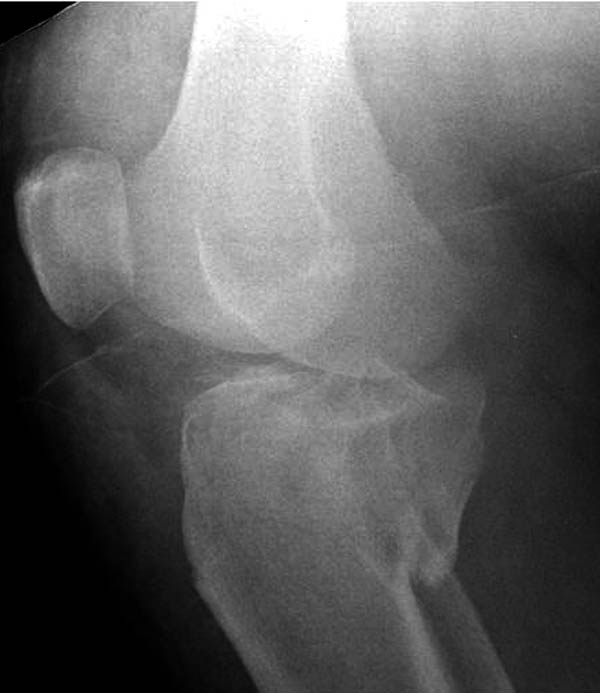

2. В аппарате для уточнения анатомии повреждения (костного) нужно выполнить КТ (лучше в аппарате, а не до него). Там скорее всего увидим не только импрессию наружного мыщелка, но и перелом внутреннего со смещением.

Следовательно начинать фиксацию надо с внутреннего мыщелка и не снимая аппарата(доступ 1 задне-медиальный, ORIF, DCP 3.5 мм, LC-DCP 3.5 мм, но лучше LCP 3.5 мм), затем восстанавливать наружный мыщелок (доступ 2 - наружный парапателлярный с прямым контролем репозиции суставной поверхности, ORIF суставного компонента, LCP-PLT 5.0 мм). На втором доступе действительно можно немного сэкономить - протолкнуть пластину над костью и зафиксировать дистально из отдельного минидоступа или проколов.

На боковом рентгене, явный задний смещенный компонент. КТ поможет увидеть "вершину" перелома, куда надо поставить антискользящую пластину из заднего или задне-медиальнего доступа. Для стабилизации боковой колонны традиционный боковой доступ через Girdle tubercle с длинной блокирующей пластиной. Одна задняя подпорка не удержит медиальную колонну, требуется длинная медиальная пластина.